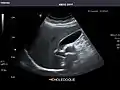

Gallbladder

Gallbladder: No stones, wall thickening, or pericholecystic fluid.

Bile duct